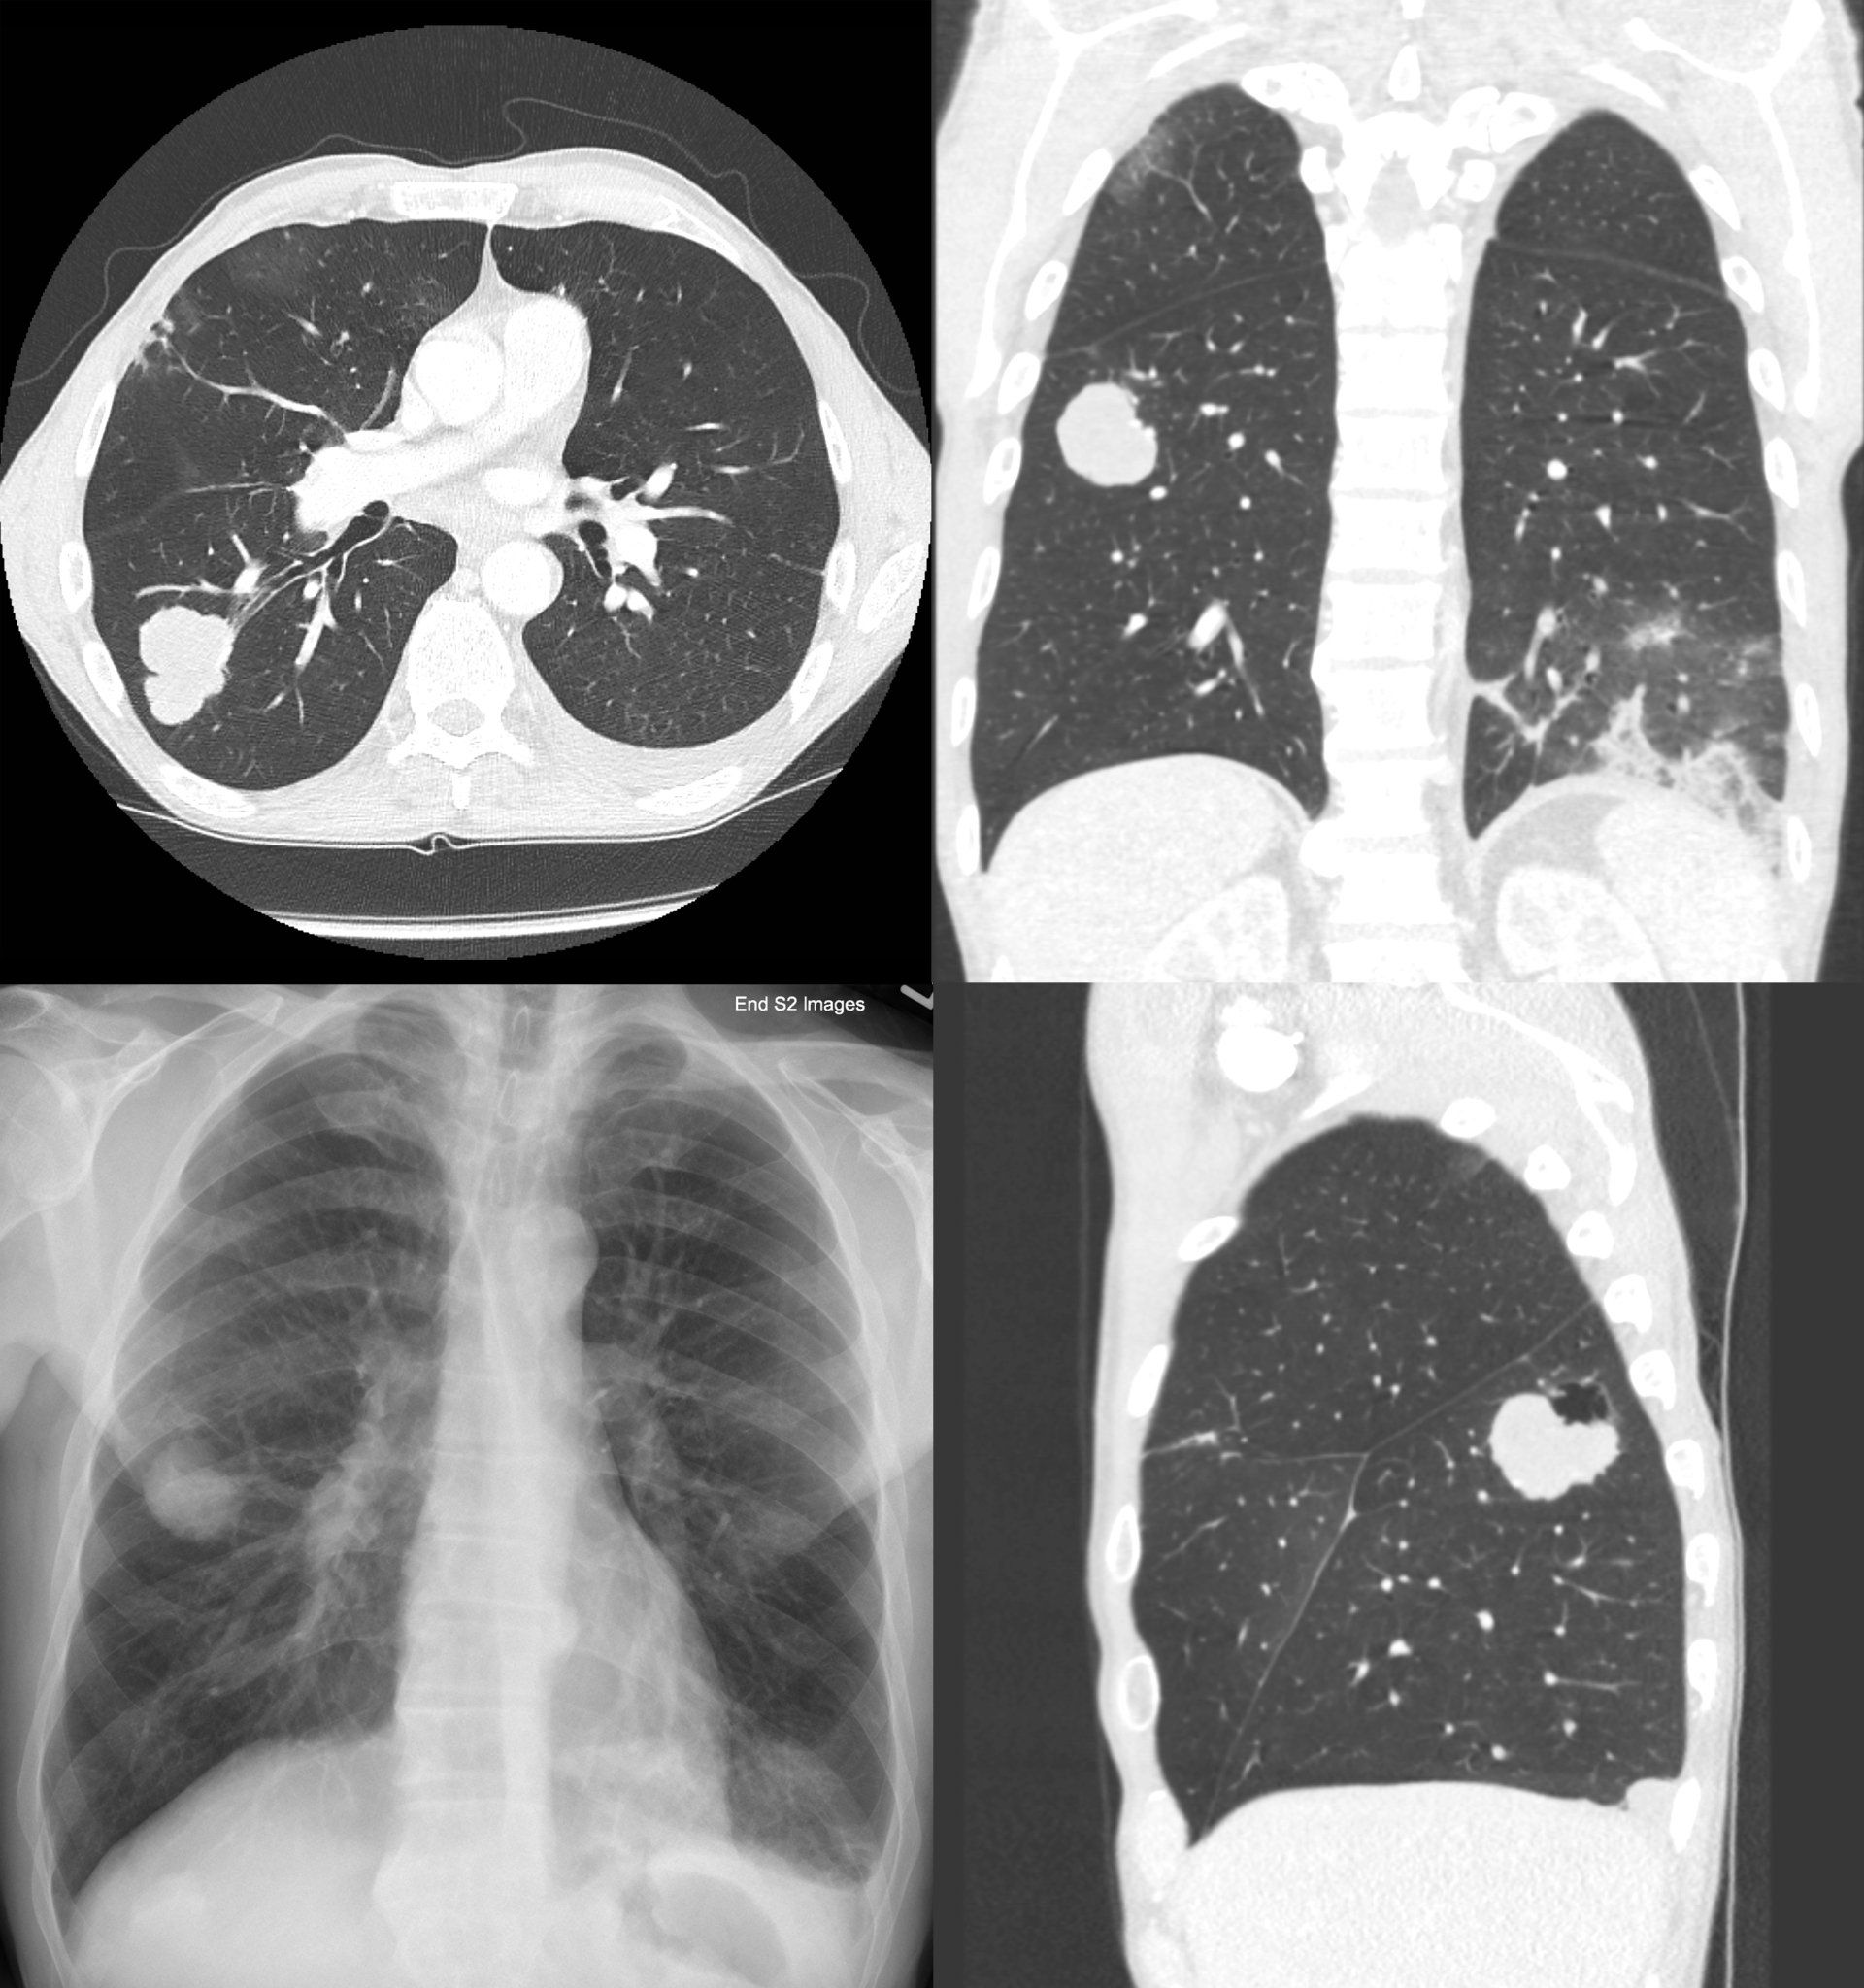

Si tratta di una TAC torace ad alta risoluzione acquisita a strato sottile (1 mm o comunque < 2 mm), con scansioni dalla base polmonare agli apici in ispirazione profonda.

La HRCT torace è un esame che studia gli spazi polmonari, il cui dettaglio è di fondamentale importanza per determinare od orientare correttamente un sospetto diagnostico. Rappresenta un'eccellenza radiologica per lo studio della malattie interstiziali polmonari e in particolare riveste un ruolo fondamentale nella diagnosi della fibrosi polmonare idiopatica (IPF), riconoscendone (o escludendone) il pattern radiologico tipico (UIP). La TAC torace ad alta risoluzione risulta un esame molto utile anche per individuare malattie polmonari legate a esposizione lavorativa (asbesto correlate e polmoniti da ipersensibilità), frequentemente sottostimate poiché misconosciute dal punto di vista diagnostico, e risulta fondamentale nelle condizioni di urgenza/emergenza causa di insufficienza respiratoria acuta (IRA).